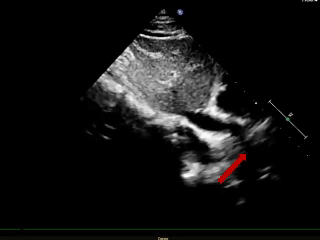

术后6个月随访

超声报告:(1)房间隔封堵器位置正常,伞盘可见部分降解,各瓣叶形态活动未见异常,右心比例稍大,左房室腔不大,心包腔内未见液性暗区; (2)多普勒检查:房水平未见残余分流;心功能:室壁运动协调,未见节段性异常;(3)先天性心脏病房间隔缺损封堵术后(可降解)未见残余分流。